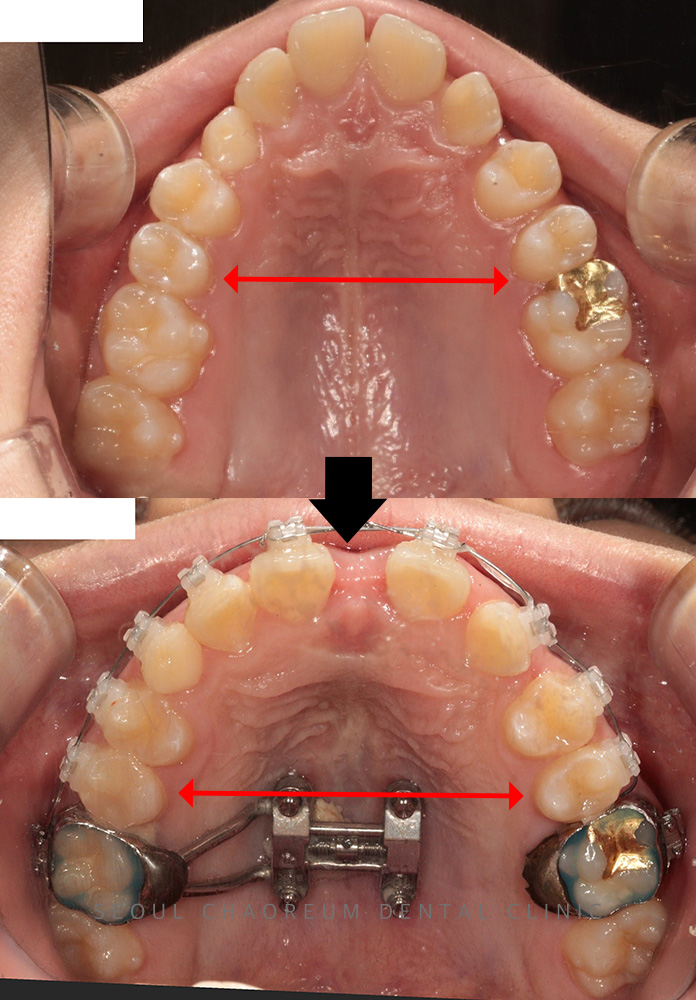

병점치과 아래 앞니 브릿지 치료가 가능한가요? 치아는 단순히 음식을 씹는 도구를 넘어, 발음과 얼굴 인상, 저작 균형까지 영향을 주는 중요한 구조물입니다. 특히 아래 앞니는 겉으로 잘 드러나는 부위인…